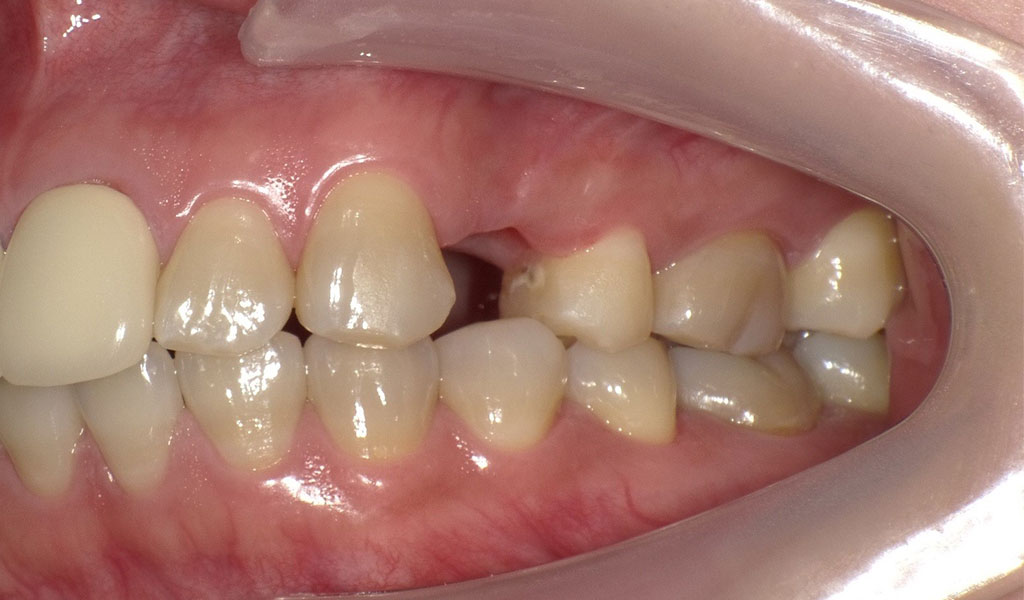

30代女性・横浜市在住。左上4番の詰め物の奥に虫歯ができてしまい、脱離。他院にて相談したがセカンドオピニオンとして当院を受診。当院にて左上4番を抜歯後、インプラント治療。人工歯はジルコニア人工歯。スクリューリテインにて固定しました。

Before2

After2

左上4番インプラント治療

左上4番を抜歯後、通常手術にて、左上4番の骨に即時にインプラントを埋め込みました。

インプラントと骨がしっかり結合するまで術後3ヶ月待ち、インプラントの上に人工の歯を被せる治療を行いました。